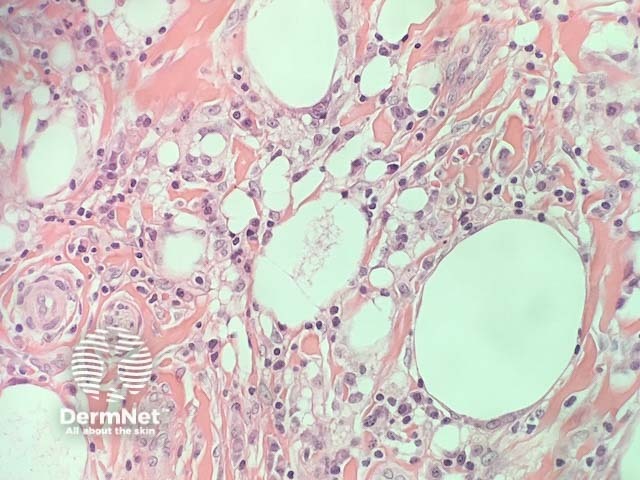

In sclerosing lipogranuloma, the histopathology shows fat necrosis, histiocytes, giant cells with extensive fibrosis and hyalinization. There are polymorphous vacuoles of the foreign material and pseudocysts where there is more extensive accumulation of material (figures 1,2).

Figure 1

Figure 2